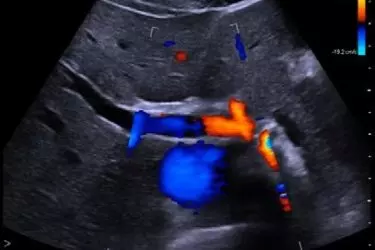

Arteries are the blood vessels which take blood away from the heart and supply blood to various body parts. There are two carotid arteries found in the neck region which supply blood to the brain and face. Due to unhealthy diet and lack of exercise, fat deposits take place in all the blood vessels. This condition is called atherosclerosis. Colour Doppler study of Carotid arteries is done on an ultrasound machine with colour doppler function. In this study, the flow of blood in the twin arteries is measured alongwith Carotid Intima Mean Thickness (CIMT). This is the thickness of the walls of carotid arteries. Higher the CIMT value, narrower are the carotid arteries. When the blood supply to the face or brain is restricted, the chances of brain stroke are increased. Most of the times, the blood supply is restricted at the junction of the bifurcation of the carotid artery where one branch goes to the brain and the other branch goes to the face. This is the reason that most common stroke symptom is paralysis of one side of the face or one side of the body.

Atherosclerosis of the Carotid arteries is treated in the same manner as Atherosclerosis of other blood vessels in the body. The patient can be put on healthy diet and strict exercise regimen. Blood thinners are prescribed and finally Angioplasty can be done to put a stent in the artery for restoring the blood supply. Every patient suffering from Heart Disease, Hypertension or Diabetes should get Carotid Doppler Study to find out the CIMT Values for both the arteries. Timely action can prevent a large number of strokes. Stroke is a very debilitating disease as the recovery of stroke patients is very late and very time consuming. The patient becomes dependent on others for even the basic functions of day to day life. CT Angiography of the Brain and Neck Vessels can also be done for finding out atherosclerosis of the Carotid arteries but the test is not only expensive but also requires the patient to have good kidney function. CT Scan also has harmful radiation which is not the case with Colour Doppler Study.

The cost of carotid colour doppler is in the range of Rs. 3000 - 3500 at our different centres. Most of the radiologists are trained in doing Ultrasound Scans but not all the radiologists are comfortable in doing the colour doppler studies. Proper training and adequate experience is required for performing different types of colour dopplers. The ultrasound machine and its features also play a very important role in doing good quality colour doppler scans. Colour Doppler is actually a study of blood vessels in the body and achieves its objectives at a much lower cost than Contrast Angiography on CT Scan or MRI which also studies the flow of blood in the arteries and veins. Contrast CT Angiography of Neck Vessels would cost in the range of Rs. 10000- 12000. We have multiple centres in the NCR Region and you can get appointment at any of our centres by calling on the numbers +91-8800188334 / 8800188335 / 8800188336.